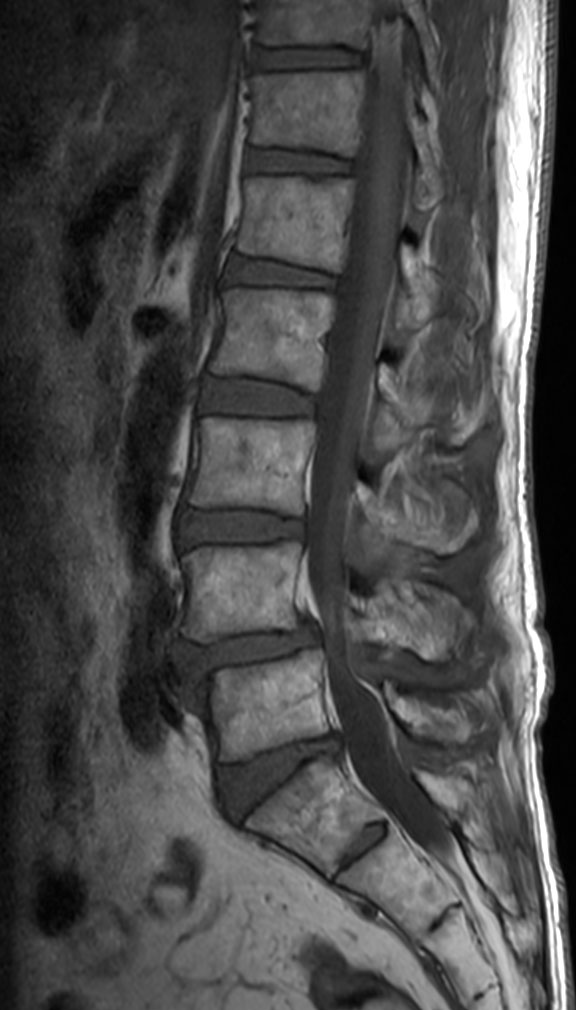

Lumbar Spine disc herniation

Patient with a lumbar spine disc herniation.